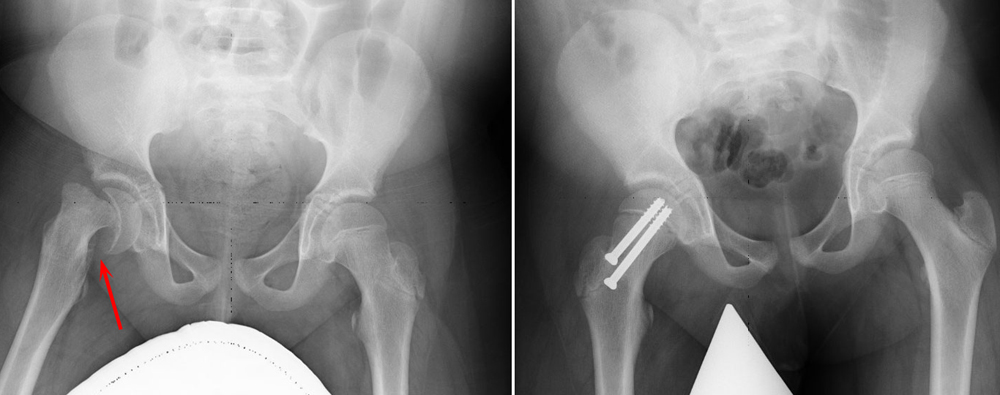

11yo male presents to pediatrician with a 3 week history of a painful left hip. He and his parents denies any inciting or traumatic event and he denies fever, chills, recent illness, or past symptoms. On physical examination, he has a noticeable limp and you elicit pain with passive internal rotation of the hip. Radiograph is below.

Diagnosis – Slipped Capital Femoral Epiphysis

2. Diagnosing SCFE on plain radiographs is accomplished by drawing a parallel line from the lateral femoral neck towards the femoral head. This line is called Klein’s Line. In normal patients, this line should intersect the lateral portion of the femoral head. In SCFE patient, it does not.

3. The mainstay of management of SCFE is operative stabilization by way of percutaneous in situ fixation